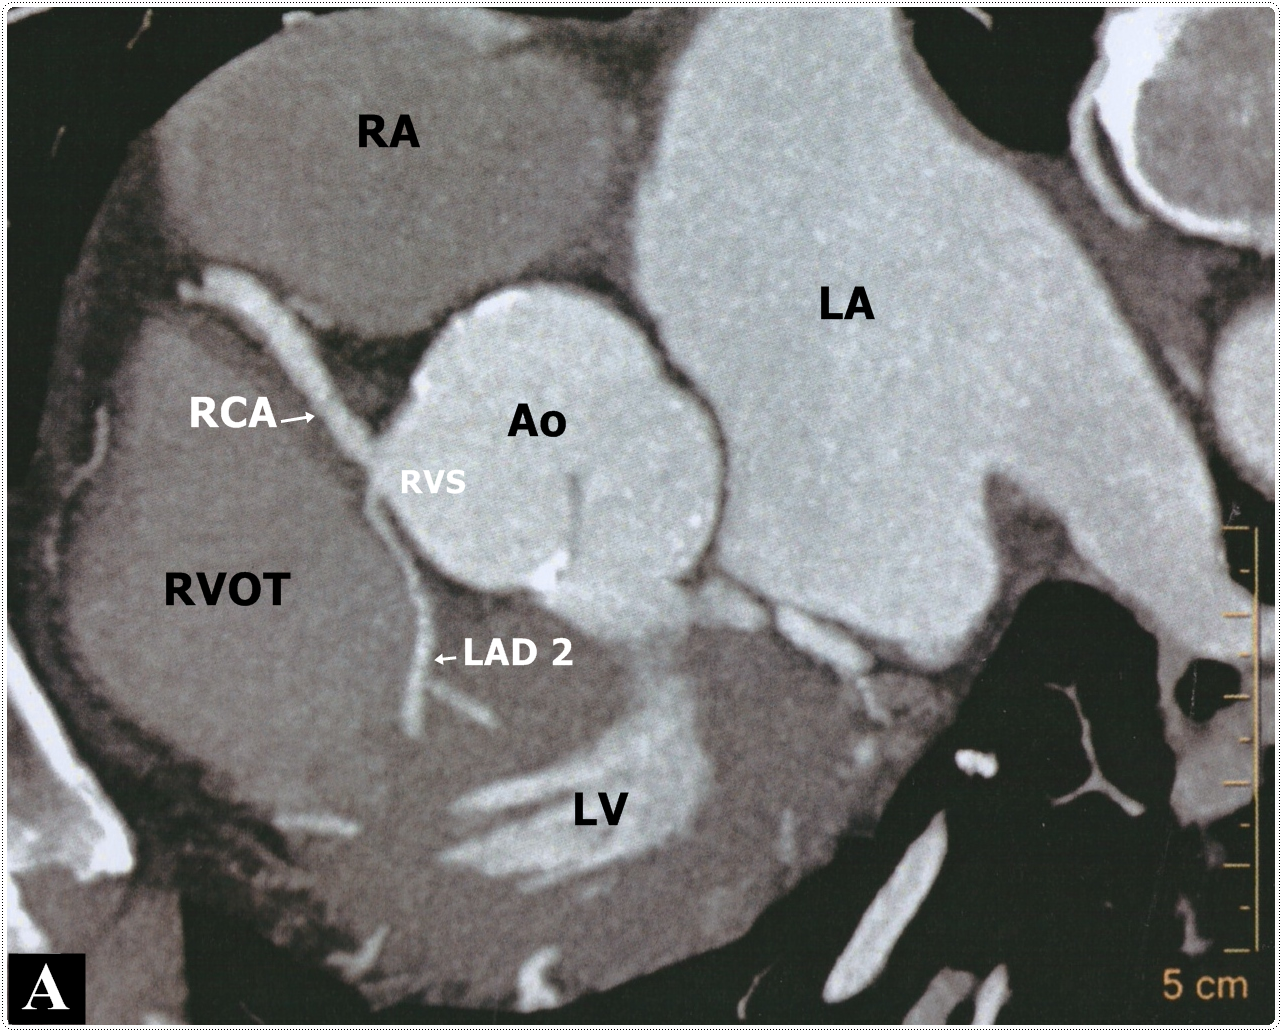

Figure 2: A. CT angiography axial section. RA: Right atrial. LA: Left atrial. Ao: Aortic root. RVS: Right Valsalva sinus. RVOT: Right ventricle outflow tract. LV: Left ventricle. RCA: Right coronary artery. LAD 2: Long left anterior descending artery. B. 3D volume CT angiography. LMCA: Left main coronary artery. LAD: Left anterior descending artery. LCx: Left circumflex artery.

Selective right coronary angiography revealed a dominant right coronary artery (RCA), without lesions (Figure 1B), during the injection, contrast media dyes unselectively an artery that comes very close to the origin of the RCA. Selective angiography of this vessel reveals that it is the middle - distal segment of the LAD which is directed right to left and return to its position on the AIVS giving a septal branch near its origin and a second diagonal branch (Figure 1D) establishing the diagnosis of a dual LAD system (Figure 1C), the proximal segment of the long LAD was narrower than the middle segment without an arteriosclerotic lesion and no compression was observed during systole. CT angiography identified the anomalous origin of long LAD from the Right Valsalva Sinus (RVS) near the origin of the RCA, and passing between the aortic root and RVOT providing a second diagonal branch without atherosclerotic lesions (Figure 2A&2B), and ending in the distal AIVS. The lesion in the posterolateral branch was successfully treated with the implant of 3.0 x 28 mm everolimus eluting stent.